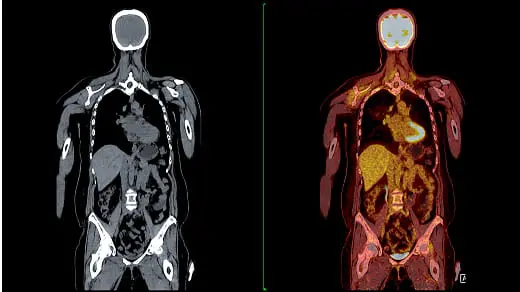

全身をくまなくがんをスクリーニングするには、全身MRIやPET/CTなどの画像検査に加え、胸部CTや消化管内視鏡など、複数の検査を組み合わせる必要があり、費用が約20万円以上に及ぶことも。

がんの全身精密検査例

全身MRI または PET/CT

1. 胸部CT

2. 頭部MRI

3. 胃内視鏡

4. 大腸内視鏡

個別で受診した場合の相場感

• 全身MRI:8~12万

• PET/CT:7~15万

• 胸部CT:2~4万

• 頭部MRI:3~7万

• 胃内視鏡:1.5~4万

• 大腸内視鏡:2~6万

Q 他の検査(PET/CTやMRI)との違いは何ですか?

A PET/CTやMRIは、苦手ながんやカバーされない部位があります。また、腫瘍部分が1cm程度の大きさにならないと発見できません。その点 マイクロCTC検査は全身のがんリスクを一度の検査で判明でき、腫瘍が1cm以内の大きさでも、間葉系のがん細胞に悪性化したものは検 出することが可能です。